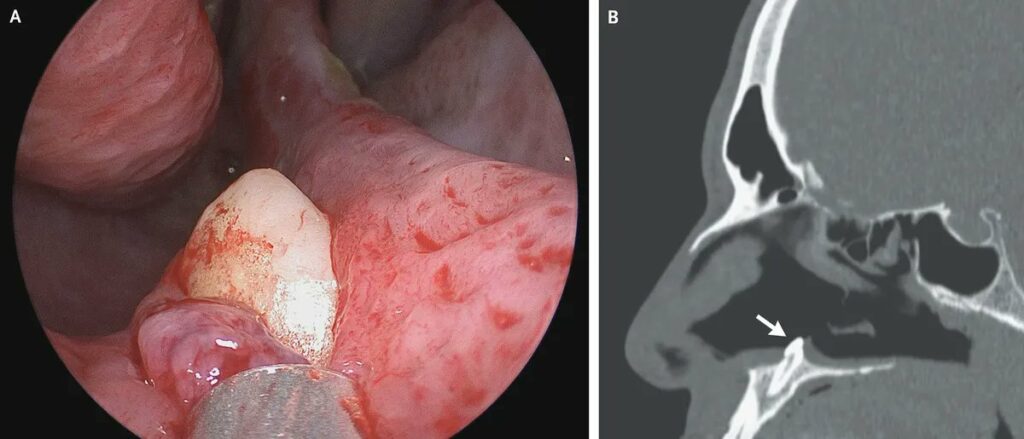

كان الرجل قلقًا من انسداد فتحة أنفه اليمنى باستمرار، ووجد طبيب الأنف والأذن والحنجرة الذي فحص المريض أنه قد نما سنًا إضافيًا في أنفه، بحسب ما ذكرت صحيفة ” New England Journal of Medicine”.

وكشف الفحص عن حاجز منحني متشكل من “كتلة بيضاء صلبة” في فتحة الأنف، وأكد التصوير المقطعي أن السن هو سبب صعوبة التنفس.

وفقًا للأطباء، فإن ظهور السن في مكان غير نمطي هو مرض نادر للغاية يحدث في حوالي 0.1% من السكان.وبعد عملية جراحية، أزال الأطباء السن من تجويف الأنف بطول 14 ملم وعرض 10 ملم. وخلص الأطباء إلى أنه “بعد ثلاثة أشهر من العملية، اختفت أعراض احتقان الأنف لدى المريض”.